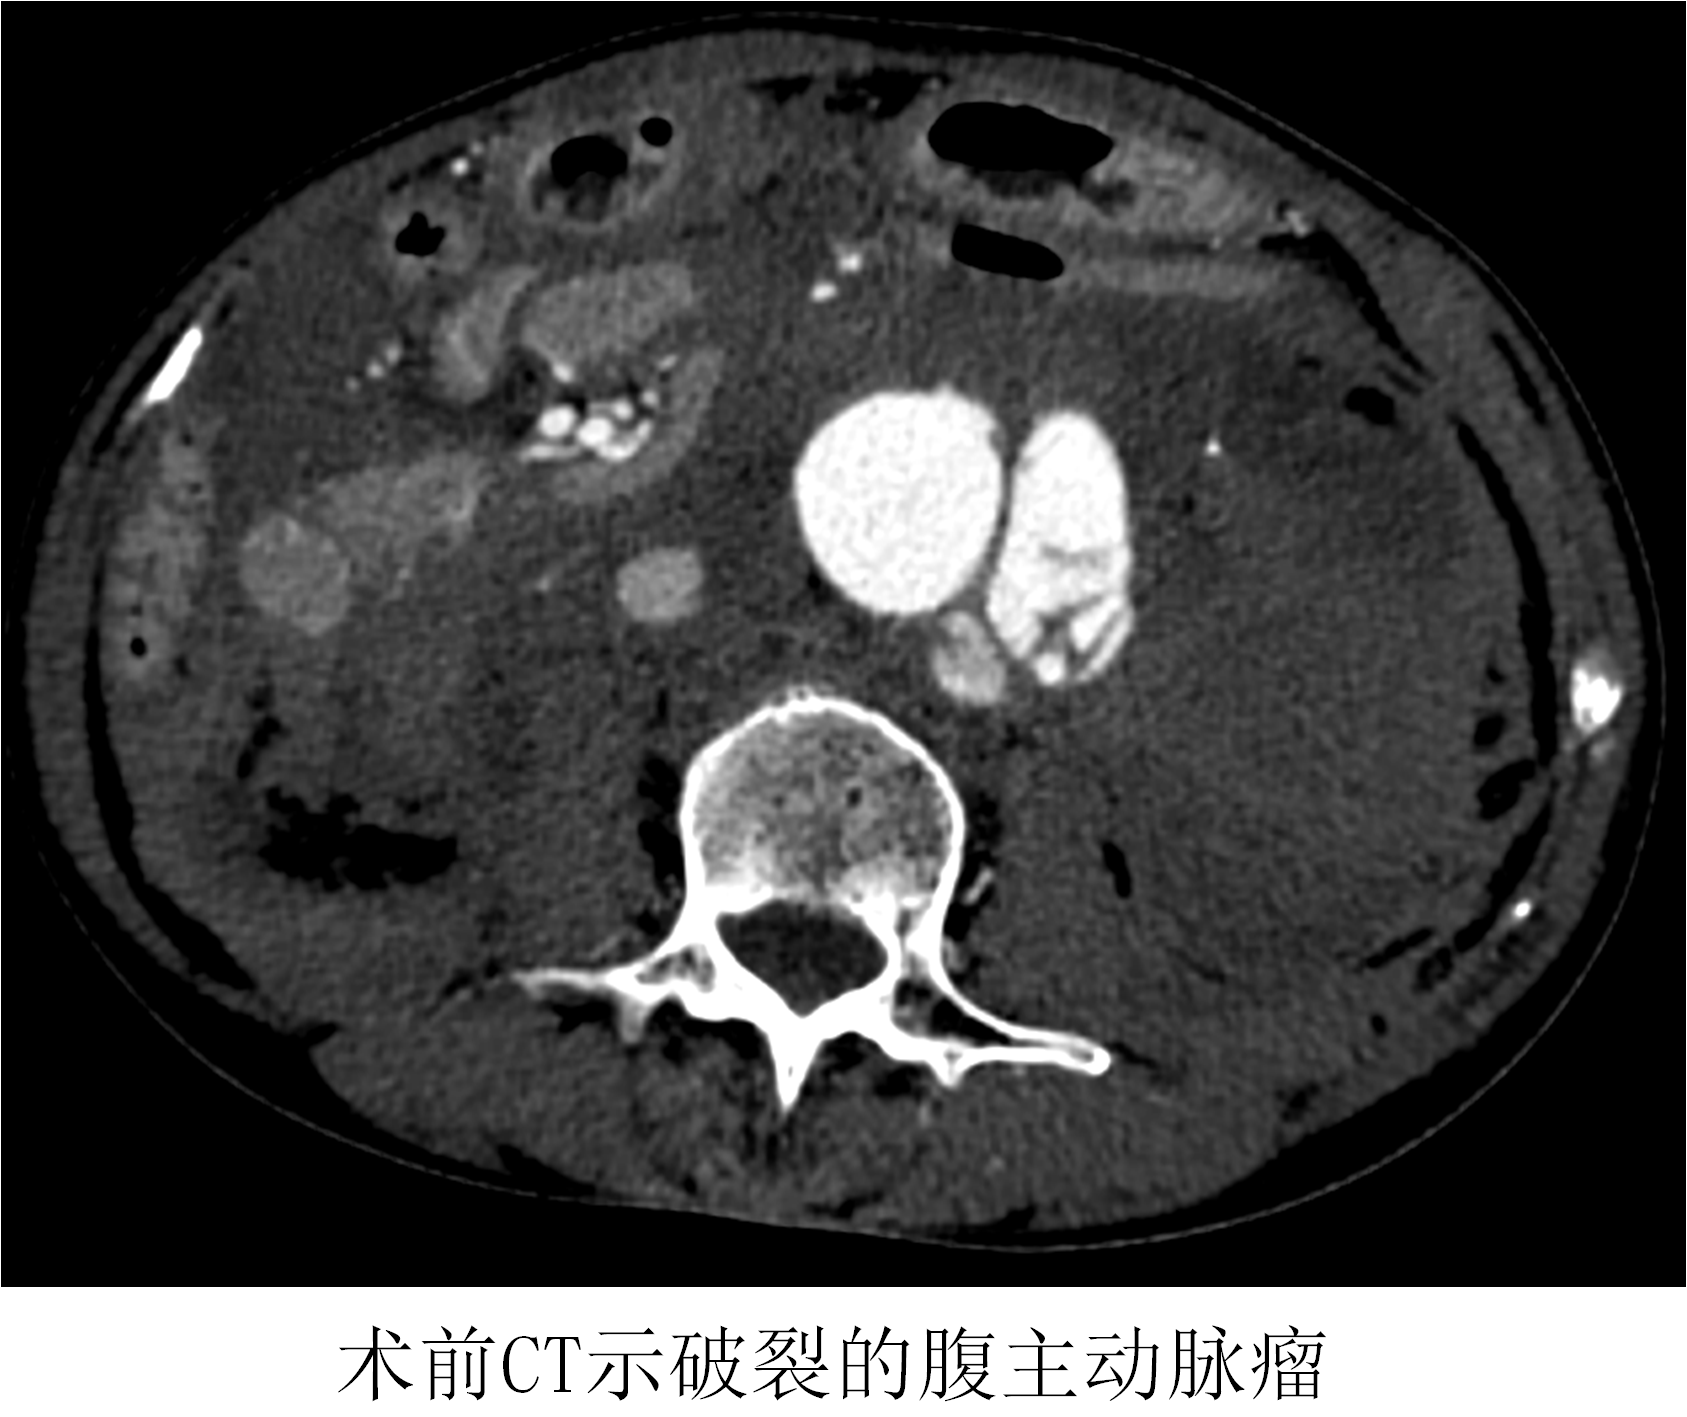

時(shí)間就是生命!在來(lái)不及全麻的情況下,薛冠華當(dāng)機(jī)立斷,局麻手術(shù)。手術(shù)由薛冠華主刀、倪其泓和王預(yù)立醫(yī)師共同協(xié)助,在麻醉醫(yī)師黃丹、手術(shù)室護(hù)士夏悅和放射科技師馬鋆的配合下緊張進(jìn)行。薛冠華通過(guò)精準(zhǔn)定位,在避免影響內(nèi)臟血管的同時(shí),采用腔內(nèi)技術(shù)在短短30分鐘內(nèi)就將腹主動(dòng)脈瘤的破口通過(guò)覆膜支架封堵,有效阻止了進(jìn)一步出血;颊叩难獕洪_(kāi)始回升,情況逐漸平穩(wěn),手術(shù)順利完成;颊咿D(zhuǎn)入重癥監(jiān)護(hù)室后意識(shí)慢慢恢復(fù),術(shù)后10天復(fù)查CT顯示破裂的腹主動(dòng)脈瘤隔絕良好,已于近期康復(fù)出院。